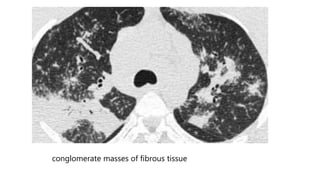

 Progressive fibrosis in sarcoidosis may lead to peribronchovascular (perihilar)

conglomerate masses of fibrous tissue.

 The typical location is posteriorly in the upper lobes, leading to volume loss of

the upper lobes with displacement of the interlobar fissure.

 Other diseases that commonly result in this appearance are:

 Silicosis , Tuberculosis , Talcosis

conglomerate masses of fibrous tissue

 Progressive fibrosisin sarcoidosis may lead to peribronchovascular (perihilar) conglomerate masses of fibrous tissue.  The typical location is posteriorly in the upper lobes, leading to volume loss of the upper lobes with displacement of the interlobar fissure.  Other diseases that commonly result in this appearance are:  Silicosis , Tuberculosis , Talcosis

• 25.

conglomerate masses offibrous tissue